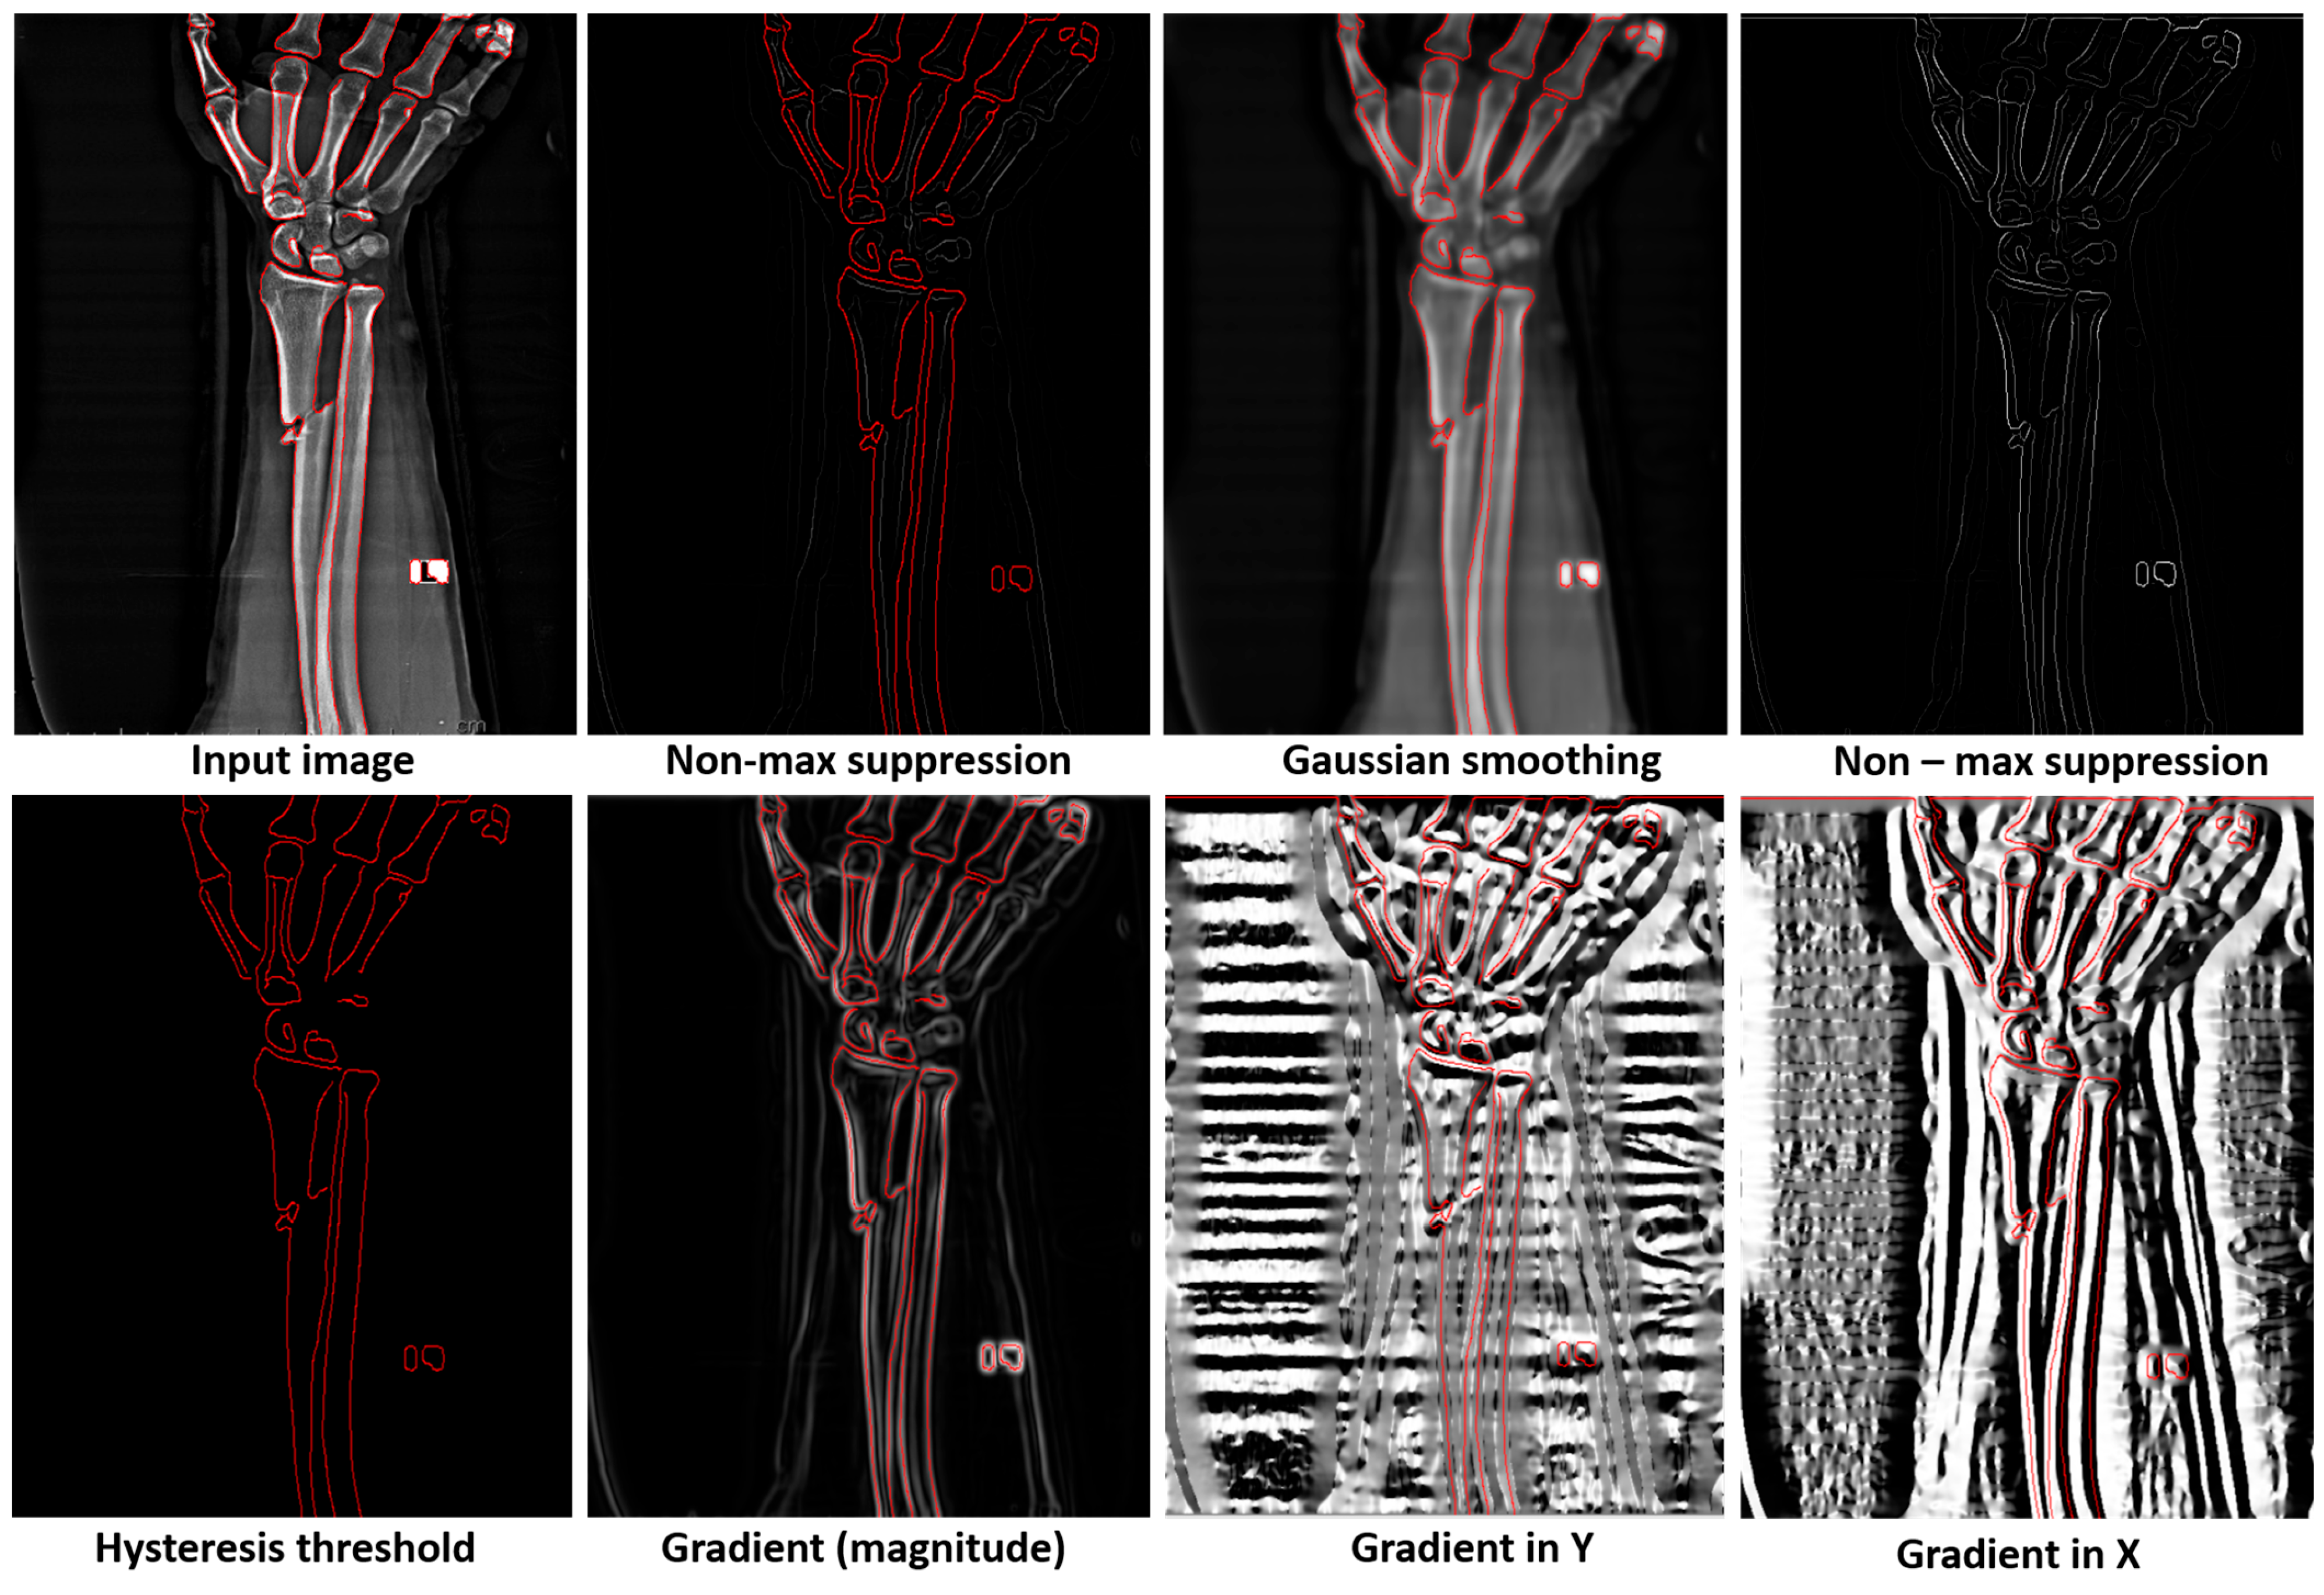

- We integrate the Canny edge detector within our model architecture to enhance its ability to identify subtle structural discontinuities indicative of bone fractures. This addition significantly improves the model performance in detecting minor and complex fractures.

4.3. Comparative Analysis of Edge Detection Techniques